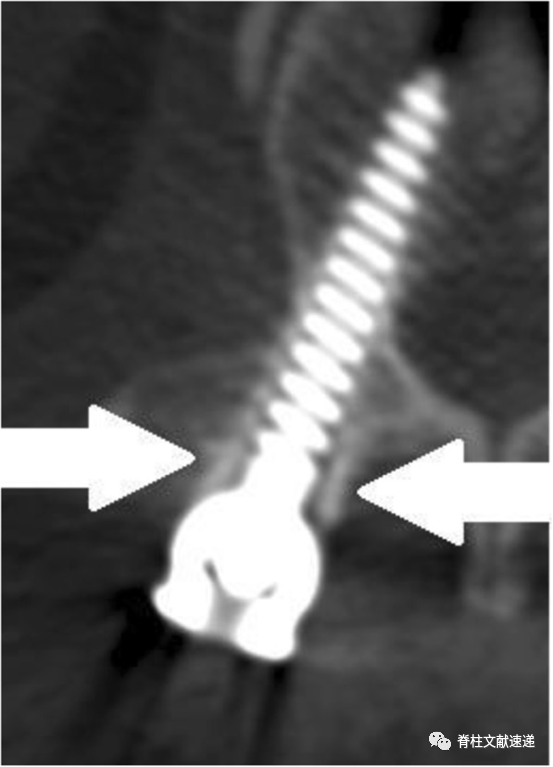

CT检查发现螺钉松动的征象

本文中CT显示的松动螺钉